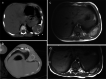

Materials and methods: We collected data of children with thoracic mesenchymal hamartomas who were treated at our institution from 2005 to 2020 using various percutaneous techniques. Techniques included radiofrequency thermoablation, microwave thermoablation (microwave thermoablation) and cryoablation.

Results: Five children were treated for chest wall hamartomas; one child showed bilateral localization of the mass. Two children underwent microwave thermoablation, one radiofrequency thermoablation and two cryoablation; one child treated with cryoablation also had radiofrequency thermoablation because mass volume increased after the cryoablation procedure. The median reduction of tumor volume was 69.6% (24.0-96.5%). One child treated with microwave thermoablation showed volumetric increase of the mass and underwent surgical removal of the tumor. No major complication was reported.